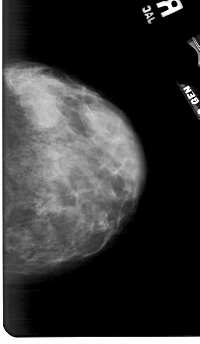

A_1797_1.RIGHT_MLO

RIGHT_MLO LINES 5491 PIXELS_PER_LINE 3046 BITS_PER_PIXEL 12 RESOLUTION 43.5 NON_OVERLAY